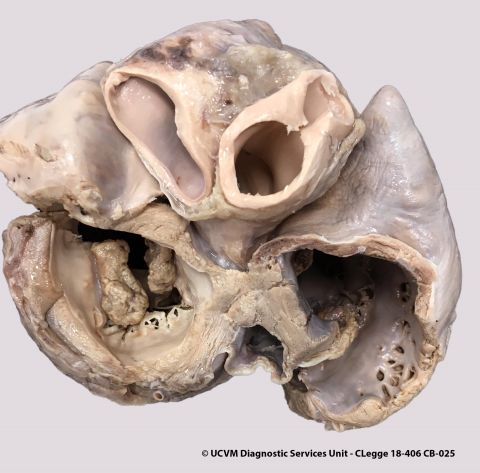

Species: Equid, Horse

Heart, AV valve

Vegetative valvular endocarditis

Irregular yellow-red or yellow-gray vegetations on the valve leaflets, with underlying ulcerations